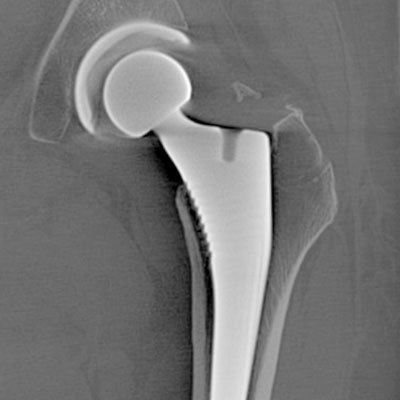

Mit unserem neuen CT-Gerät (CT steht für „Computertomographie“. Die Computertomographie ist ein bildgebendes Verfahren, das mithilfe von Röntgenstrahlen und Computertechnologie detaillierte Querschnittsbilder des Körpers erzeugt) der neuesten Generation leisten wir einen Quantensprung in der präzisen Untersuchung. Diese fortschrittliche Technologie liefert überlagerungsfreie Querschnittsbilder des Körpers und ermöglicht eine Visualisierung von Gewebsregionen, die mit herkömmlichen Röntgenuntersuchungen nicht erreichbar sind.

Besonders in Bereichen, in denen feinste Strukturen wie Blutgefäße, Lunge oder winzige Knochen beurteilt werden müssen, bietet die doppelt so hohe Bildschärfe dieses CT-Geräts signifikante Vorteile. Klare und präzise Diagnosen erhöhen die Sicherheit für die Patienten und erleichtern die Therapieentscheidungen. Die zusätzliche Nutzung der Energieinformation liefert umfassendere diagnostische Aussagen, wodurch auf zeit- und kostenintensive Zusatzuntersuchungen oft verzichtet werden kann.

Unser neues CT zeichnet sich durch eine deutlich reduzierte Strahlendosis und kürzere Untersuchungsdauer aus, dank der hohen Geschwindigkeit, mit der die Scanner in Sekundenbruchteilen 3-D-Schnittbilder erstellen. Dieses Niveau der Diagnostik setzt neue Maßstäbe in der Sportorthopädie im Professor Citak Gesundheitszentrum.